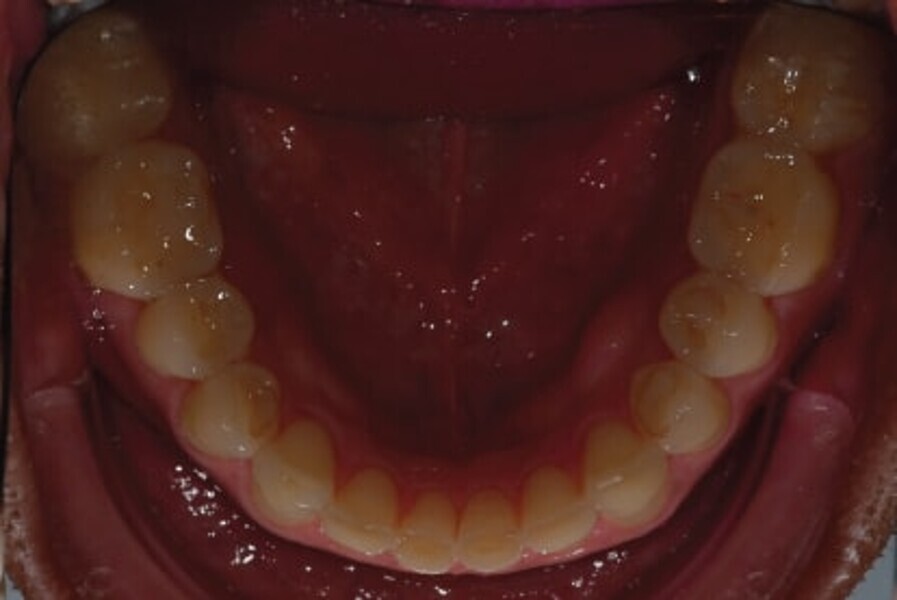

Fig. 3: Intraoral

photograph prior to treatment, occlusal view of mandible.